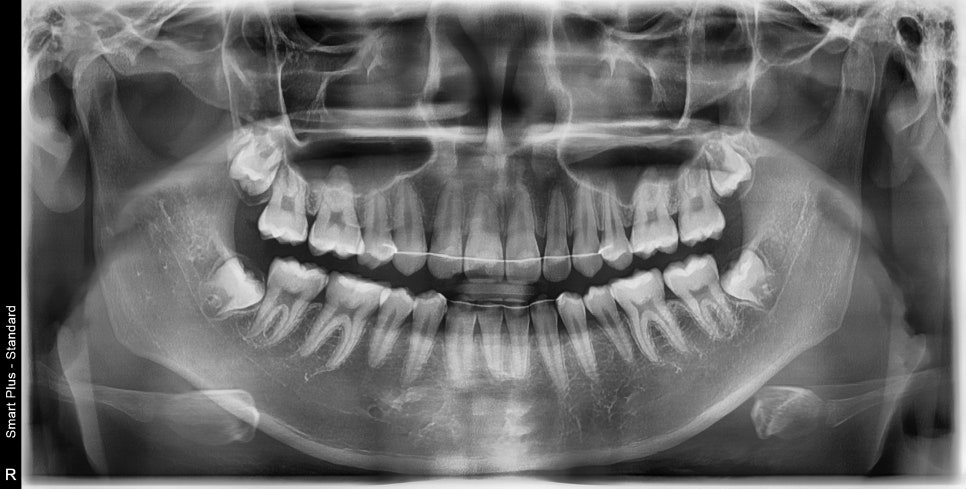

아래쪽 두개가 없을 때 가장 쉬운 방법은 위쪽도 2개의 치아를 없애는 겁니다.

이 친구는 약간의 돌출도 보이고 있었기 때문에 위쪽 치아를 두개 발치했었습니다.

약2년의 치료기간이 걸렸으며 올해 초에 정기검진을 왔습니다

치료가 끝난지 약 3년정도 지난 모습인데 긴밀한 교합으로 인해 치료결과가 잘 유지되고 있는 것 같습니다.

오랜 시간이 지난 뒤 엑스레이에서도 부작용이 관찰되지 않고 잘 유지되고 있네요